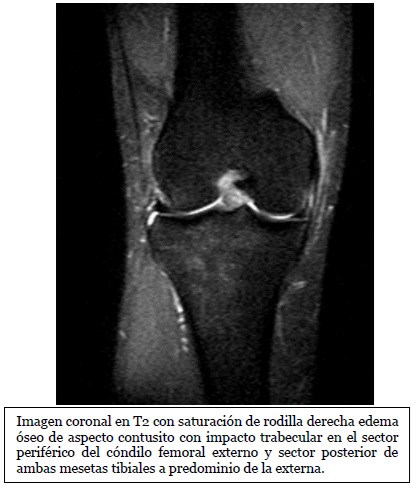

Imagen coronal de secuencia potenciada en T2 con saturación grasa de la rodilla derecha en paciente con lesión por traumatismo en valgo. Edema óseo en la

Fuente: https://epos.myesr.org/posterimage/esr/seram2014/124014/mediagallery/577012